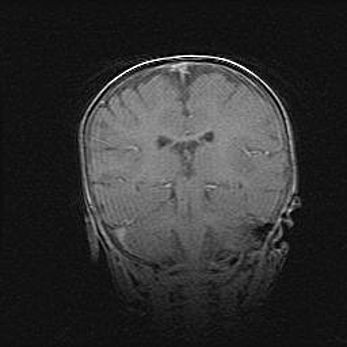

Церебральная ишемия II.

Возраст: 5 дней

Вес: 3400 г

Пол: женский

Окружность головы: 35 см

Срок гестации: 39 недель

Церебральная ишемия – это заболевание, характеризующееся недостаточностью (гипоксией) либо полным прекращением (аноксией) снабжения мозга кислородом по причине закупорки одного или нескольких сосудов. Это приводит к  что метаболическим расстройствам различной степени тяжести в тканях головного мозга, развитию коагуляционных некрозов и гибели нейронов.